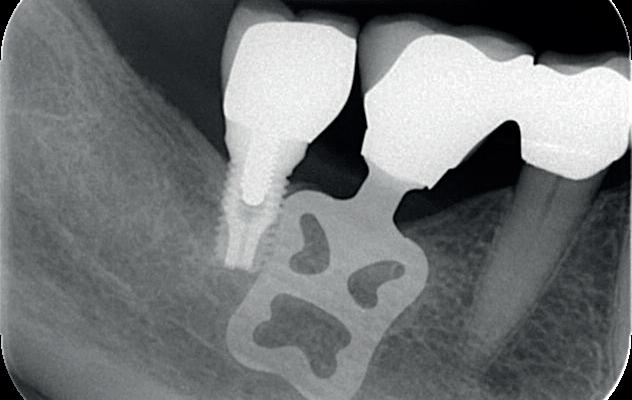

In het onderfront werd autoloog bot geoogst uit de kin regio ten behoeve van augmentatie (afbeelding

9. Botopbouw onderfront

10. OPT-implantaten

9). In de bovenkaak werd bilateraal een sinuslift uitgevoerd. Aansluitend werden in beide kaakhelften implantaten geplaatst (afbeelding 10).